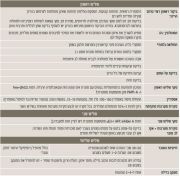

| 08:30, 16 בספטמבר 2023 | לוואי מאוחרות1.png (קובץ) |  |

590 קילו־בייטים | Motyk | 1 | |